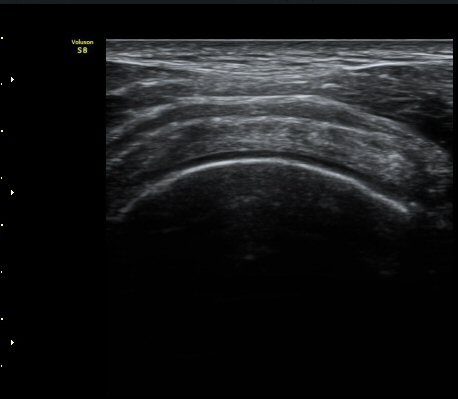

±Ø»ó°Ç Á¾´Ü¸é°Ë»ç¿¡¼­ ±Ø»ó°Ç ÆÄ¿­Àº º¸ÀÌÁö ¾ÊÀ¸³ª »ó¿Ï°ñ ´ë°áÀý°ú °ñµÎ ÀÌÇàºÎÀ§¿¡¼­

ÇÇÁú°ñ ¿¬°á ¼Ò½Ç°ú ¹Ì¼¼ÇÑ °ñÆíÀÌ °üÂûµÊ(»çÁø 3, 4, 5).

±Ø»ó°Ç Ⱦ´Ü¸é°Ë»ç¿¡¼­ ±Ø»ó°Ç ±ÙÀ§ºÎ¿¡¼­´Â ƯÀÌ ¼Ò°ßÀ» º¸ÀÌÁö ¾ÊÀ¸³ª ±Ø»ó°Ç ¿øÀ§ºÎ¿¡¼­

ÇÇÁú°ñ ¿¬°á ¼Ò½Ç°ú ¹Ì¼¼ÇÑ °ñÆíÀÌ °üÂûµÊ(»çÁø 6, 7).